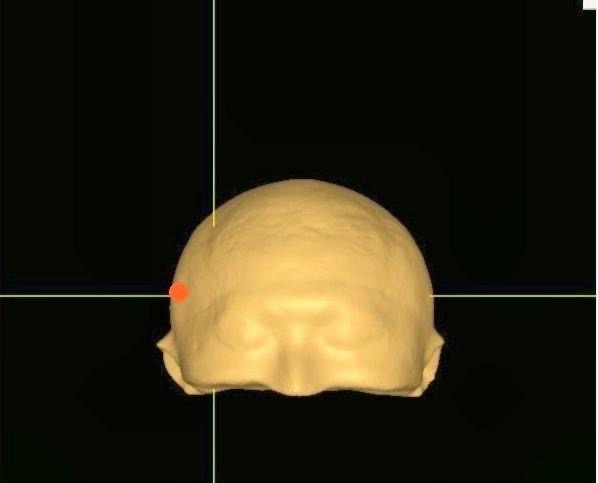

應用3D技術定位右側前額下迴(圖中橘色的指示記號)(長庚醫院提供)